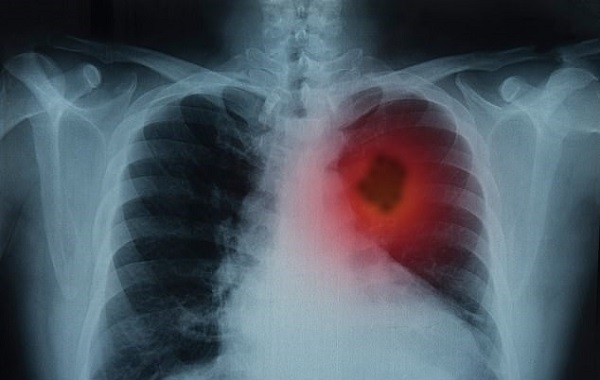

Bilim İnsanları Kanserli Hücrelerin Metastazını Durdurabilecek Bir Atılım Keşfetti

Uzmanlara göre kanserin nasıl yayıldığını anlamak daha iyi tedavilere yol açacak bir atılım olabilir. Kanser hücrelerinin, sağlıklı hücreler aracılığıyla vücuda yayılmada kullanılan bir süreci ‘ gözden kaçırdıklarını’ ve bunun, kanser hakkındaki mevcut düşünce biçimlerini tamamen değiştirdiğini keşfettiler.

Metastaz, kanser hastalarında başlıca ölüm nedenlerinden biri olmasına rağmen, şimdiye dek kanserin yayılmasını önlemek inanılmaz derecede zor olmaya devam etti. Şimdi, NALCN adlı bir proteinin kilit bir rol oynayabileceğini keşfettiler. Farelerde yapılan deneylerde, NALCN proteininin aktivitesini bloke etmenin metastazı tetiklediğini buldular.